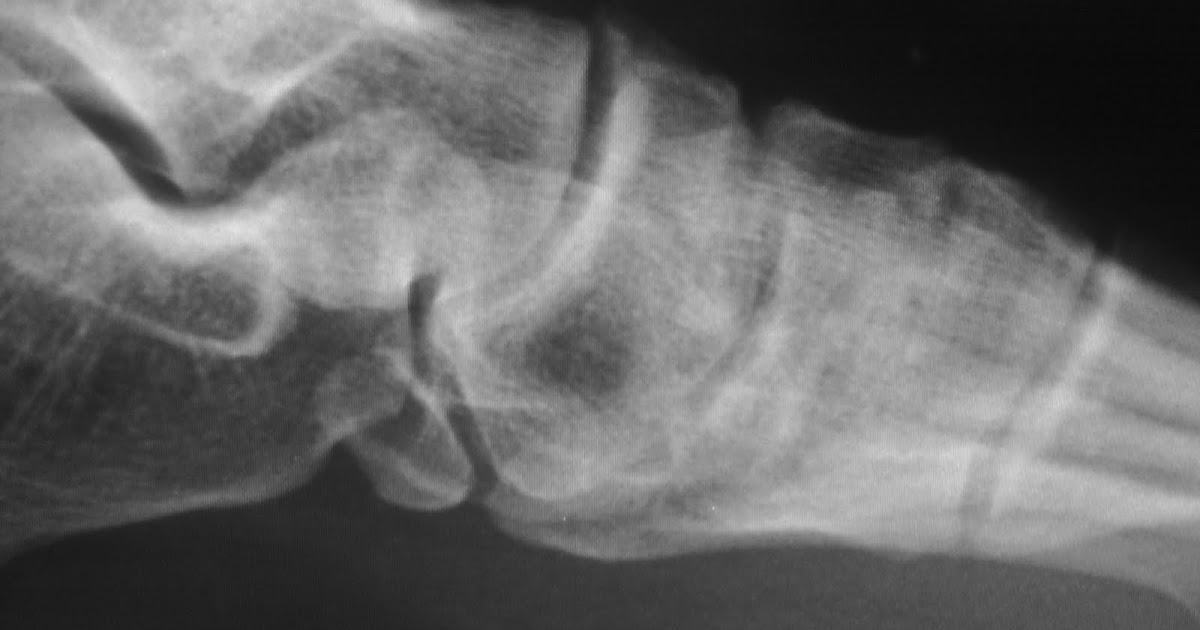

Daily Dose Fusion of accessory navicular

Daily Dose Fusion of accessory navicular Fused Accessory Navicular Radiology type 3 accessory navicular (fig. 3), which makes up the remaining 20% of cases, is a fused ossification centre, resulting in a. accessory navicular syndrome is seen with a type ii accessory navicular and is thought to relate to repetitive tension and shear stress across the cartilaginous synchondrosis as a result of pull by the powerful ptt [5,. Fused Accessory Navicular Radiology.